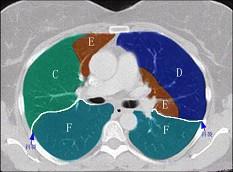

问题 结合肺段模式肺动脉干与右肺动脉层面(见图), 心室层面(见图), 主动脉弓层面(见图), 左右心房层面图(见图),选出左肺下叶的组成 ( )

选项 A、D+E+F+G+H+I+J B、C+D+E+F+G+H+I+J C、F +H+I+J D、E+F+G+H+I+J E、G+H+I+J

答案 C